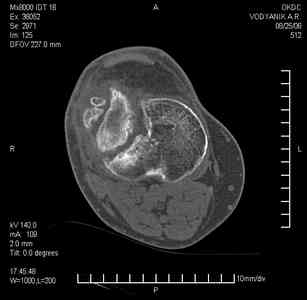

Уважаемые коллеги, В ортопедическое отделение обратился пациент: мужчина 47 лет, который в течение 4-х лет дважды получил травму костей, образующих правый коленный сустав.

В 2002 v внутрисуставной оскольчатый перелом проксимального метаэпифиза правой большеберцовой кости; в 2005 v внутрисуставной оскольчатый перелом дистального метаэпифиза правой бедренной кости.

В обоих случаях в разных лечебных учреждениях проводилось оперативное лечение переломов. При осмотре в отделении на основании результатов клинического осмотра и данных визуальных методов обследования поставлен диагноз: тугой ложный сустав дистальной трети правой бедренной кости, состояние после накостного остеосинтеза перелома типа 33-В2.2 ; несросшийся перелом надколенника; неправильно сросшийся перелом латерального мыщелка правой большеберцовой кости, состояние после металлоостеосинтеза перелома 41-В2.2; сочетанная осевая деформация правой ноги: варусная деформация правого бедра, вальгусная деформация правой голени; посттравматический артроз коленного сустава 4 ст по Kellgren-Lowrence; выраженное нарушение функции ходьбы и опоры.

Внешний вид ноги больного, данные рентгенографического обследования и избирательно выделенные компьютерные томограммы приведены в приложении. В именах КТ использовано кодирование уровня по АО, т.е. _41, например, означает проксимальную треть голени. В отделении намечен v очень предварительно v следующий план лечения: